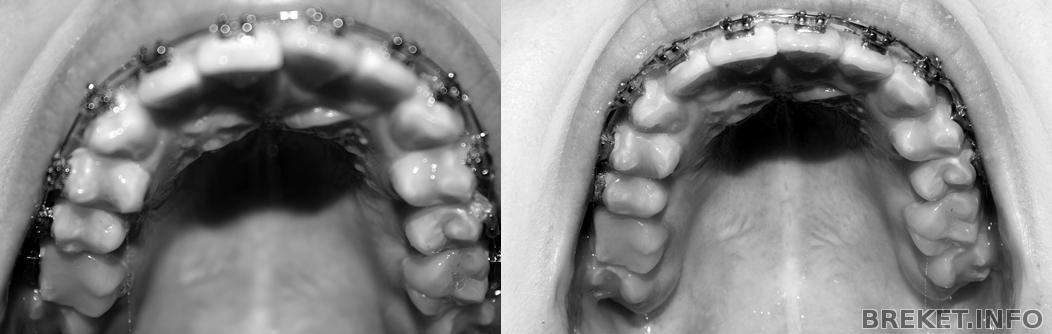

Давно я тут не отмечалась, хотя на сайт заглядываю частенько. А между тем, время идет...уже 2 года, как я в брекетах. Прогресса уже такого заметного, как в начале, нет, все двигается ооочень медленно. О снятии речи пока нет, сейчас двигаем единичку на ВЧ. А сегодня сделала фотки, посмотрела на НЧ, ужас, центр реально сдвинулся в одну сторону на целый зуб(. Сделала коллаж, смотрите.

1д.1г.2г.ВЧ